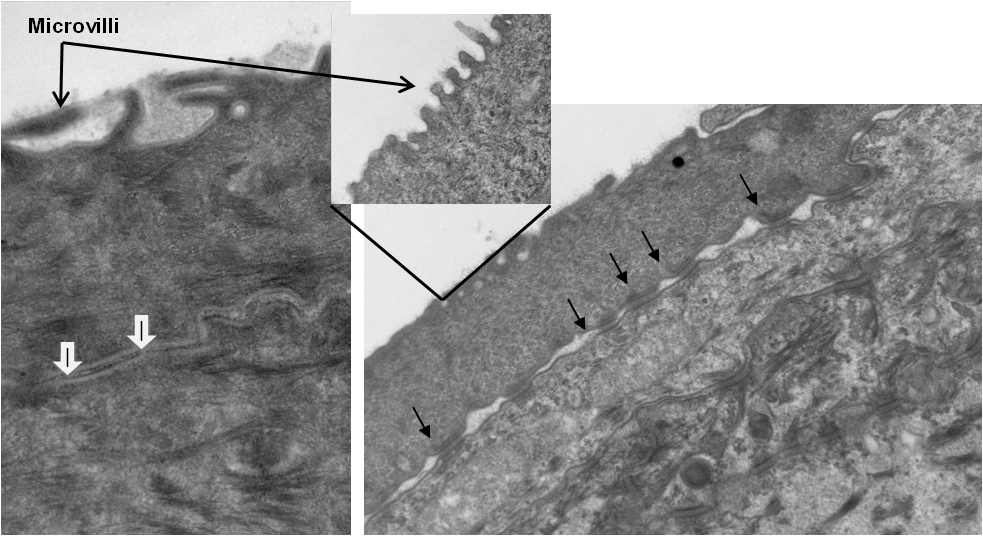

Ultrastructural features of EpiCorneal. Apical cell layer of reconstructed tissue. Open arrows point to microvilli on the surface of the tissue. Tight junctions (white arrows) and desmosomes (closed arrow) are observed at the junction of adjacent epithelial cells.

TEM Analysis of EpiCorneal illustrates the presence of 1) microvilli, 2) tight junctions (white arrows), and 3) desmosomes (black arrows)